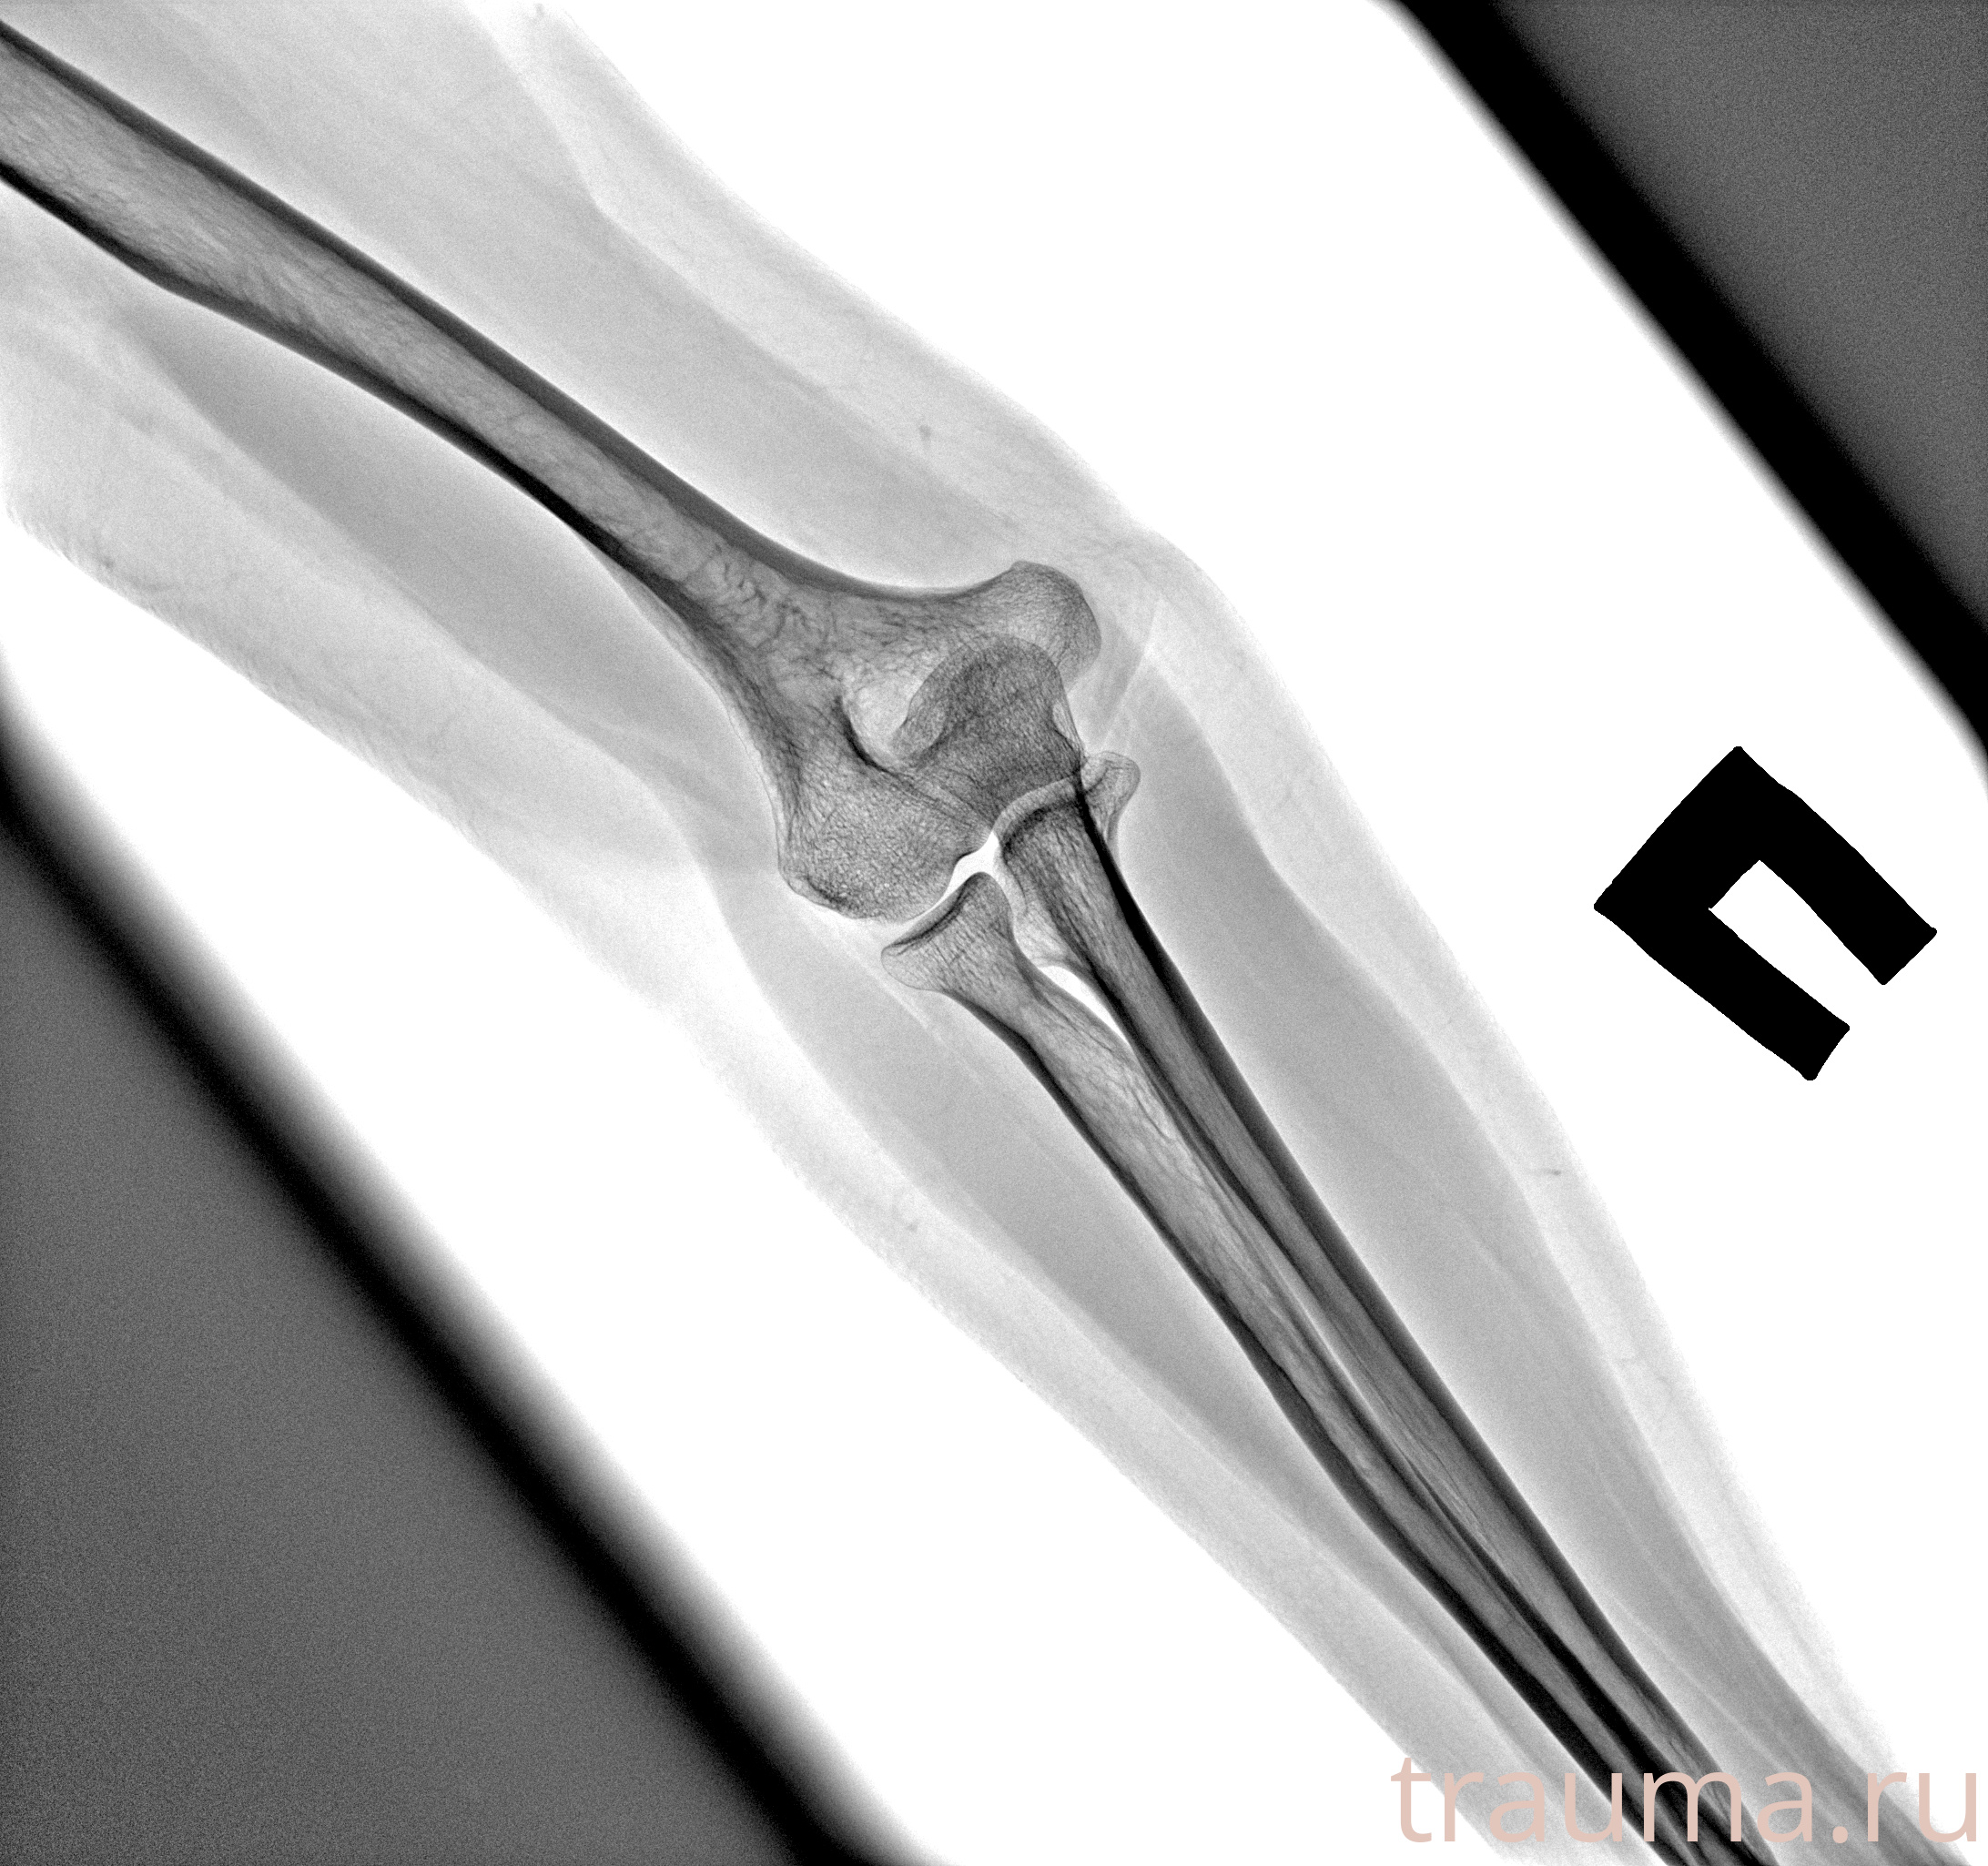

Рентгенограммы

Рентген на дому: по вашему адресу приезжает врач-рентгенолог, травматолог-ортопед с мобильным рентгеновским аппаратом, проводит диагностику травмы или заболевания, делает необходимые рентгенограммы, дает рекомендации по дальнейшему лечению. Получить качественные снимки в домашних условиях возможно благодаря уникальной методике, разработанной МосРентген Центром для института  Склифосовского